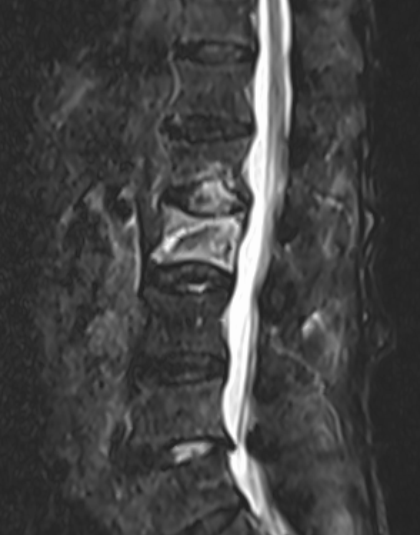

十余年来,我科室相继开展骨质疏松症的相关诊治工作,逐渐形成了自身的诊治体系,后经过整合联系,形成了以骨科二病区为龙头,联合检验科、放射科、内分泌科、血液风湿科等多学科结合、内外协作的骨松诊治MDT模式。目前采用的诊断方式有血钙及维生素ADKE检测、双能X线骨密度检测等,治疗方面也内外兼修,既可应用促成骨的四烯甲萘醌等,抑制骨吸收的唑来膦酸等药物治疗,又可采取椎体强化术、经皮穿刺椎弓根钉置入术等有效手术治疗,可结合患者自身情况,采取合适的治疗手段。开展骨质疏松诊治工作的十几年来,遵循指南,结合当地实际,总结归纳出了一套立足自身实际的诊疗体系,采取药物治疗与手术治疗相结合、因人而宜、综合施治的个体化的综合诊疗方案等。近年来,随着微创理念的推行和ERAS理念的实践,骨科二病区率先在本地区开创性的应用微创经椎间孔入路椎体强化术、经皮穿刺椎弓根钉置入术等先进治疗手段,实现立竿见影的治疗效果,深得广大患者的好评,取得了良好的社会效益和学术影响力,使桓台百姓足不出县即可享受到国内外先进的脊柱外科诊治体验。

术后术前